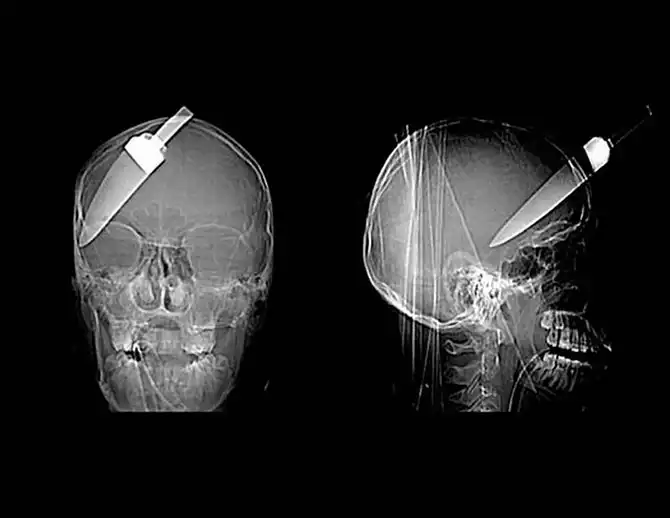

Копье от гарпуна, попавшее в голову 16-летнему мальчику на рыбалке.

Нож в голове 10-летнего мальчика. Мальчик выжил.

12-сантиметровый нож в черепе подростка.